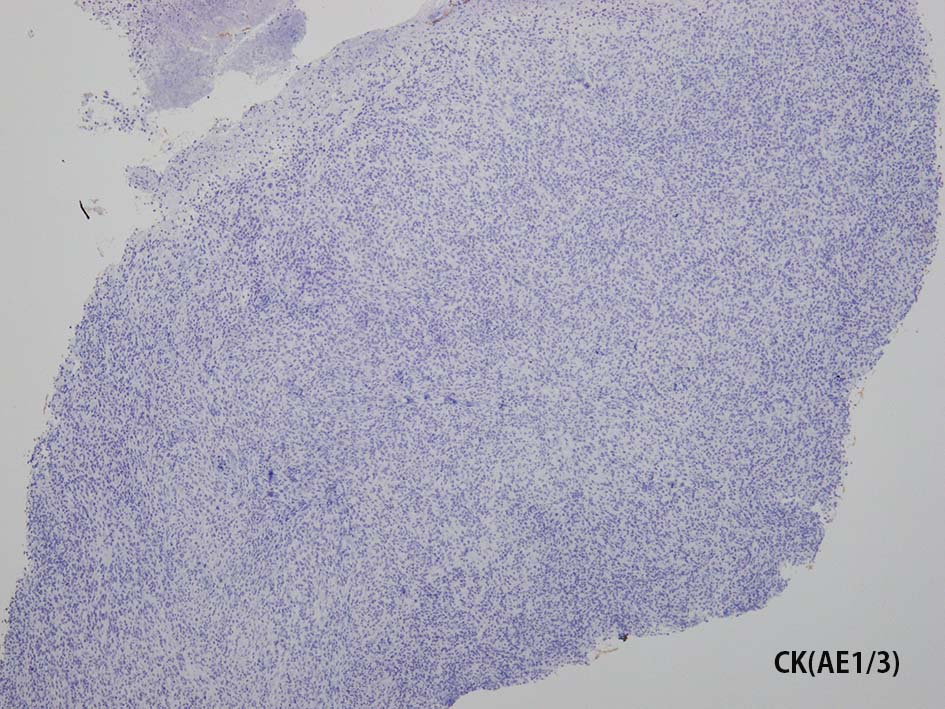

免疫染色

CD20, PAX5, CD3, CD5 リンパ球マーカは陰性. Dendritic cell marker (CD1a, CD123, Langerin, etc)は陰性. S-100, CD168, CD68(KP-1)が陽性. 組織球増殖病変と考えられた. foamy macrophageやgiant cellsはほとんど認められない. 高異型度, 多型細胞の出現はないが, MIB-1 LIが高く, mitosisも増加している, 悪性の心配あり, 治療方針の決定のため consultationを行った.

IHCの拡大像. Factor XⅢaの免疫染色画像もここに掲載する.